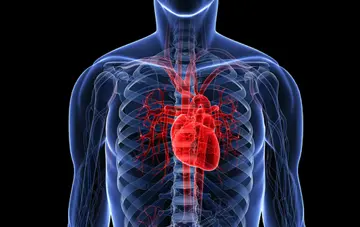

قلب - صفحه 3